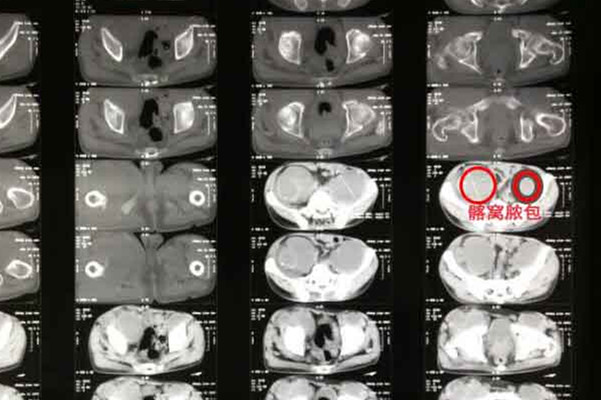

骨结核早期症状、体征多不典型,使得早期诊断困难,很多患者出现窦道、畸形等典型症状时才被确诊,容易延误治疗时机。所以当患者发现自己有关节肿胀,关节功能障碍、寒性脓肿或窦道形成、疼痛、关节畸形、神经功能障碍等。一定要及时去医疗机构就诊,查明症状引起的原因,尤其是既往有结核病史更需要引起注意。